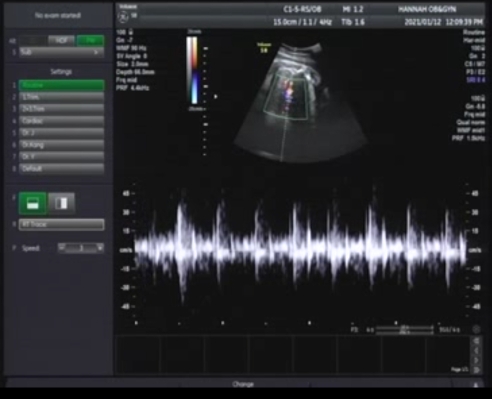

원장님과 간단히 이야기한후 초음파실로 고고~

다행이 골반쪽에 아기 머리가 잘 내려와 있고 심장소리도 좋고 탯줄이 목근처에 있지만 흔한 경우이고 크게 걱정 안해도 된다고 하셨어요.

태동이 줄수는 있지만 아예없거나 그러지만 않으면 괜찮다고 하세요.

양수량도 괜찮고 양수 부분이 뿌옇게 보이는데 태지 라고 막달때 나타나는 증상이고 출산을 준비하는 단계라고 하셨어요.

BPD 머리직경길이 9.17 (37주 2일)

AC 몸통둘레 31.92 (35주 6일)

FL 허벅지길이 7.18 (36주 5일)

WT 태아체중 3.02kg

머리크기가 작을수록 출산하는것이 유리하니 이제는 빨리 낳을수록 좋다고 하시네요.